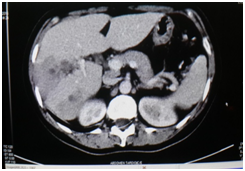

Male patient of 37years of age , white race, resident in Habana del Este municipality of Havana province, with previous health history that comes to consultation for presenting prolonged febrile syndrome with 56days of evolution, febrile peaks of 38‒39 degrees, accompanied by chills and decay. Urinary sepsis was determined as initial diagnosis so antimicrobial treatment was imposed for 10 days. There is no improvement in the clinical picture and the febrile symptoms persist. The patient is admitted to the hospital service of the Central Hospital in Havana. On physical examination, painful abdomen on palpation in the right hypochondrium and epigastrium without other alterations Laboratory tests are performed or presenting Haemoglobin: 12gl, Leucogram which yields an Eosonophilia of 66% and an Erythrosedimentation: 67. Serial blood cultures and urine cultures they were negative. Likewise, the serology was negative. Within imaging studies abdominal ultrasound reporting hepatomegaly that exceeds be 2 cm costal margin with the presence of a hypo echoic image with nodular, peripheral tendency without flow Doppler level right lobe study (Figure 1) interpreting c indicated omo pyogenic liver abscess therefore imposes treatment with antimicrobial therapy (Metronidazol EV) (Figure 1). Ultrasound: nodular, hypoechoechoic, peripheral, non‒vascularised image at the level of the right lobe of the liver clinically the patient improved his general condition, but he kept the febrile syndrome accompanied by diffuse abdominal pain. By keeping the same ultrasound image last month of treatment study it was conducted by T omografía who reported abdominal the presence of density areas of irregular appearance, in the right lobe of the liver in segments VII and VIII and endovenous study showed lesions with poor contrast capitation both Portal and late phase (Figure 2). Computed tomography with intravenous contrast: hypo dense areas of irregular appearance at the level of segments VII and VIII of the liver with poor contrast uptake Ultrasound images suggested the diagnosis of parasitosis Fasciola hepatica but also by positron raised the differential diagnosis of Focal nodular hyperplasia at que sugi river echo directed FNA that reported cytological Negative of neoplastic cells and inflammatory infiltrate with abundant eosinophils. Given this possible diagnosis, endoscopy was performed, which reported alkaline pangastropathy with a duodenal swab for negative parasitological study. Conical crown was made on several occasions resulting negative and biliary drainage was indicated to be not useful for diagnosis. In view of Clinical and Imaging suspicion of Fasciola hepatica, it was decided to perform a weekly evaluative ultrasound for 4 more weeks, observing at the end of the fourth week echogenic images, elongated with movements inside the gallbladder and an echogenic image without acoustic shadow in the canal. Coledochus suggesting the diagnostic imaging of adult Fasciola parasites in the bile ducts (Figure 3). Evolutionary ultrasound: echogenic images, free, with movement at the level of the gallbladder. The patient was referred to the Institute of Tropical Medicine (IPK) where the diagnosis was verified, imposing treatment with a single oral dose of Triclabendazole with excellent therapeutic response.

Figure 1 Ultrasound.

In hepatic fascioliasis, hypo echoic, anfractuous, well‒defined focal lesions of variable size can be observed, with a tendency to accentuate in 96% of cases (similar to the case reported), although variable echo genicity is also described . However, it is not always possible to visualize the paths that give it the characteristic stamp, so its role in acute Fasciolosis is less. The presence of per portal adenopathies is also described in 74% of cases, although this finding is nonspecific and is present in acute and chronic hepatitis, abdominal neoplasm’s, abdominal tuberculosis and sclerosing cholangitis, among other pathologies.13,14 In Biliary Fascioliasis, the role of ultrasound is greater, given that it is able to confirm parietal thickening of the common bile duct with moderate dilation , although this finding is also seen in pathologies such as sclerosing cholangitis and AIDS cholangitis . More specific is the observation of mobile structures in the gallbladder and / or common bile duct, representing the adult form of Fasciola,14,15 a finding found in the reference patient.